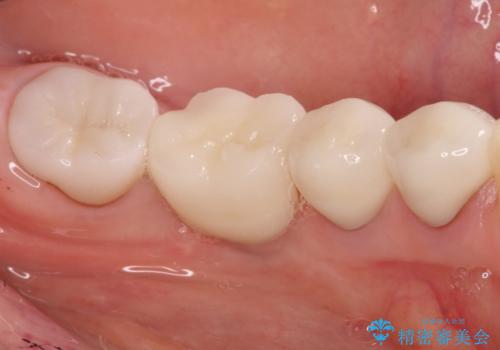

しっかりとした骨幅を獲得し、理想的な太さのインプラントを埋入することができました。

- 左下6番目の歯が欠損しており、インプラントで治療することとなりました。